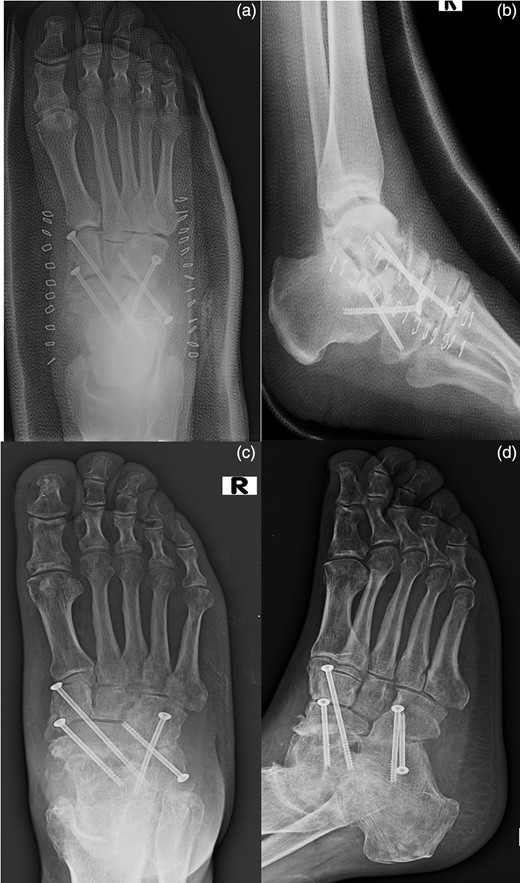

The fixation of the calcaneocuboid joint was carried out using two 4.0-mm cannulated screws. The screws were brought from proximal to distal, starting in the anterior process area and brought obliquely across into the cuboid (Fig. 4).

The placement of an autologous graft into the talonavicular joint harvested from the omolateral iliac crest (a). The fixation of the calcaneocuboid joint was carried out using two 4.0-mm cannulated screws (b) and the talonavicular joint was fused in situ using two 4.0-mm cannulated screws across the talonavicular joint (c).

At the sixth month follow-up, the patient had returned to work and remained pain free while walking, with good fusion of both joints (Fig. 5).

AP (a) and lateral (b) radiographs of the foot in the cast after the surgical time. AP (c) and lateral (d) radiographs of the foot at the sixth month follow-up.